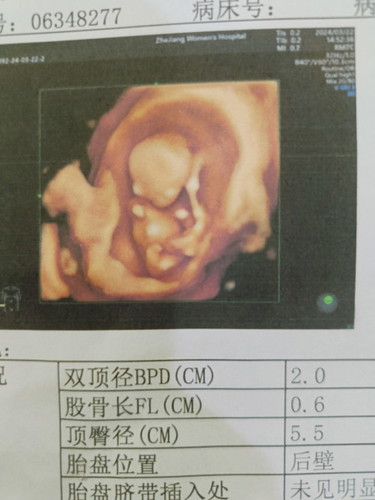

ท้อง14สัปดาห์

ดูยังไงค่ะว่าได้ผู้หญิงหรือผู้ชาย

น้องยังเล็กอยู่และภาพที่แม่ให้ดูก็ไม่เห็นเพศน้องค่ะ